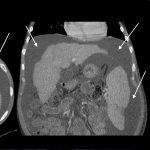

ABDOMINAL/PELVIC CT-SCAN WITH IV & ORAL CONTRAST

- Density similar to water (transudative ascites): typically between -10 and + 10 HU

- Does not enhance with oral contrast: typically this should not occur (unless there is bowel perforation/connection/fistula to the GI tract and the peritoneum).

- Density slightly above water (exudative ascites): can be above 15 HU

- Does not enhance with IV contrast: typically this should not occur, however delayed enhancement of ascites can occur in some cases. Perfused organs should appear significantly brighter then surrounding ascites.

The gallery below organizes examples of how ascites will appear on a abdominal/pelvic CT-scan with the usage of both IV and oral contrast. Click on the thumbnails below to open up the gallery: